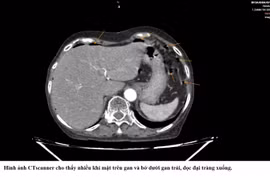

Sau khi nhập khoa, bệnh nhân được các bác sĩ tiến hành hội chẩn, chụp cắt lớp vi tính và thực hiện thêm các xét nghiệm cận lâm sàng cần thiết. Trên cơ sở đó, ê-kíp điều trị quyết định phẫu thuật nội soi bóc u xơ tử cung kích thước lớn.